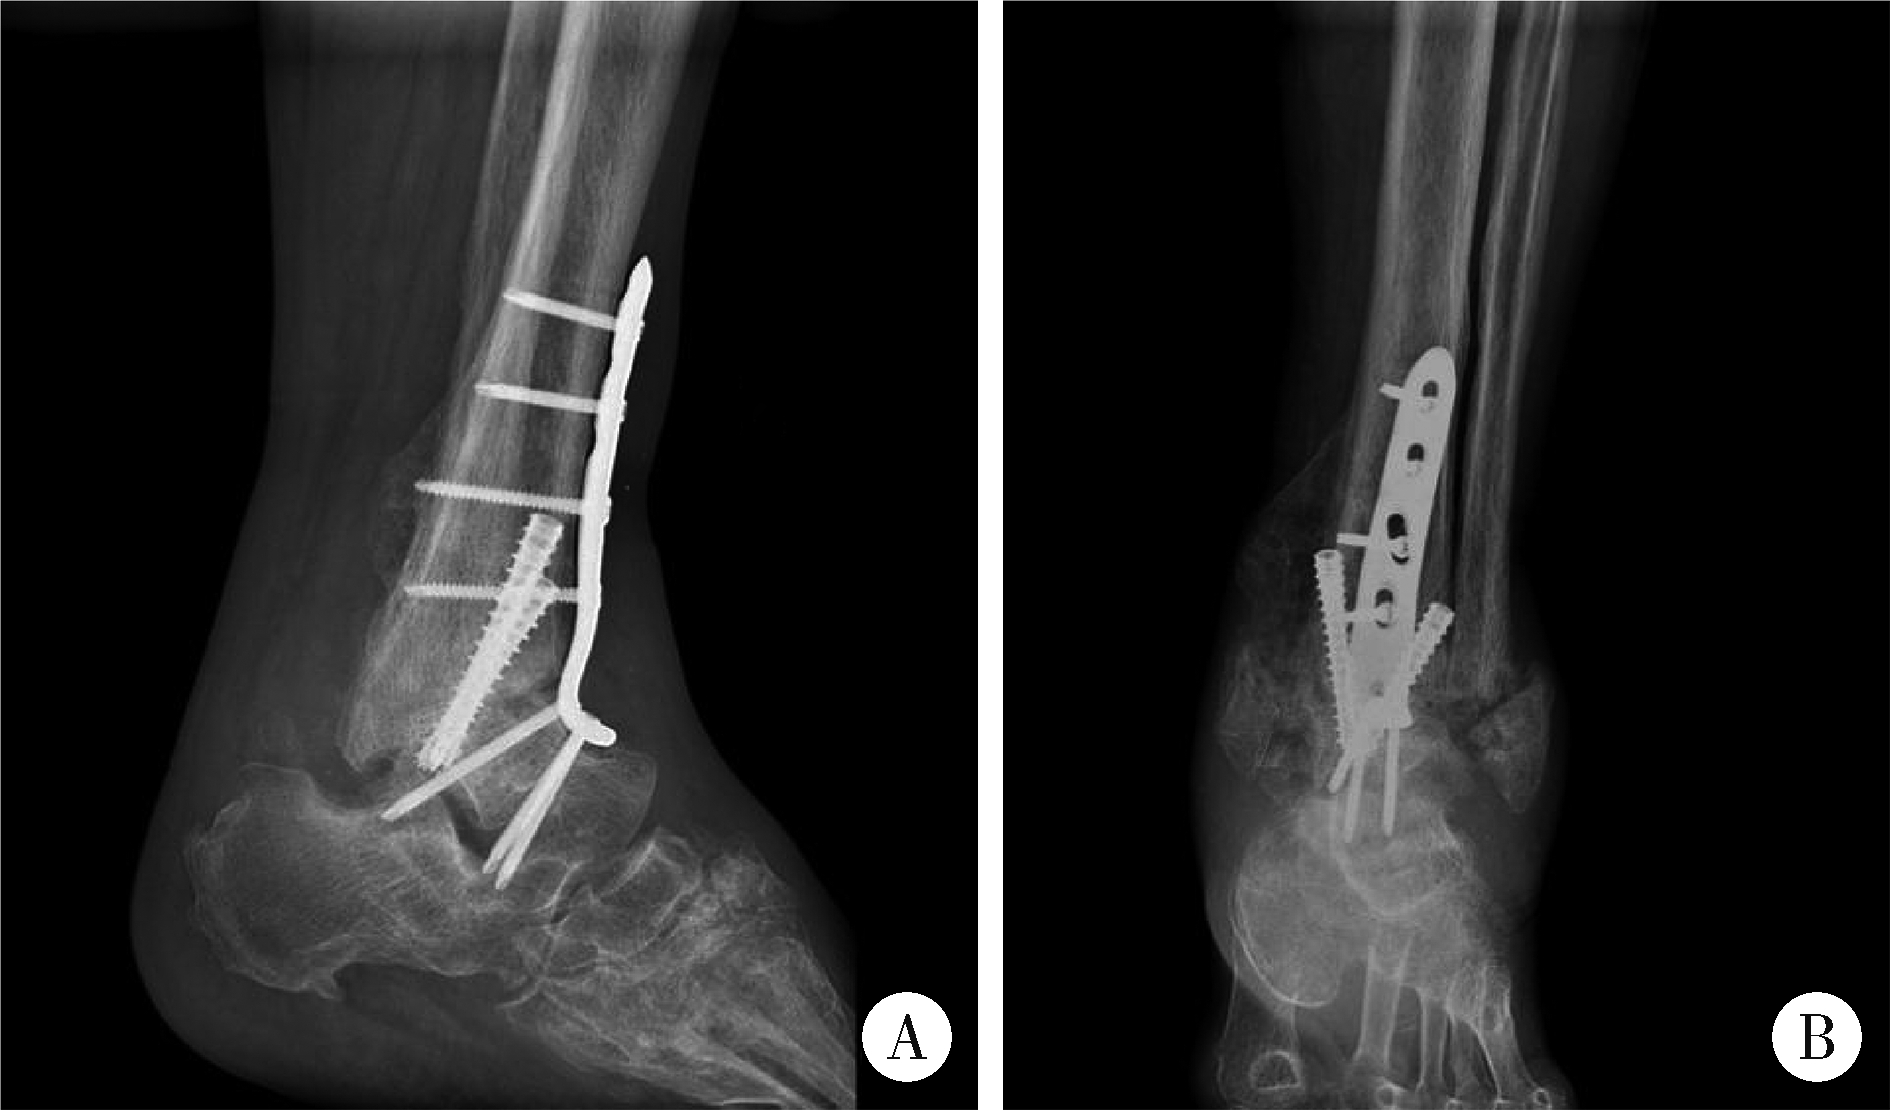

Figure 2

Weight-bearing ankle radiograph A, anteroposterior view; B, lateral view. Weight-bearing ankle radiograph shows malalignment of the left ankle joint with severe bony destruction of both the medial and lateral malleoli, as well as intra-articular loose bodies."